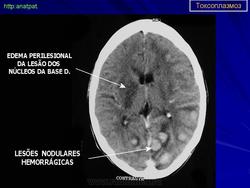

Церебральный токсоплазмоз.

Церебральный токсоплазмоз

Случаи и цифры

Дифференциальная диагностика изображения